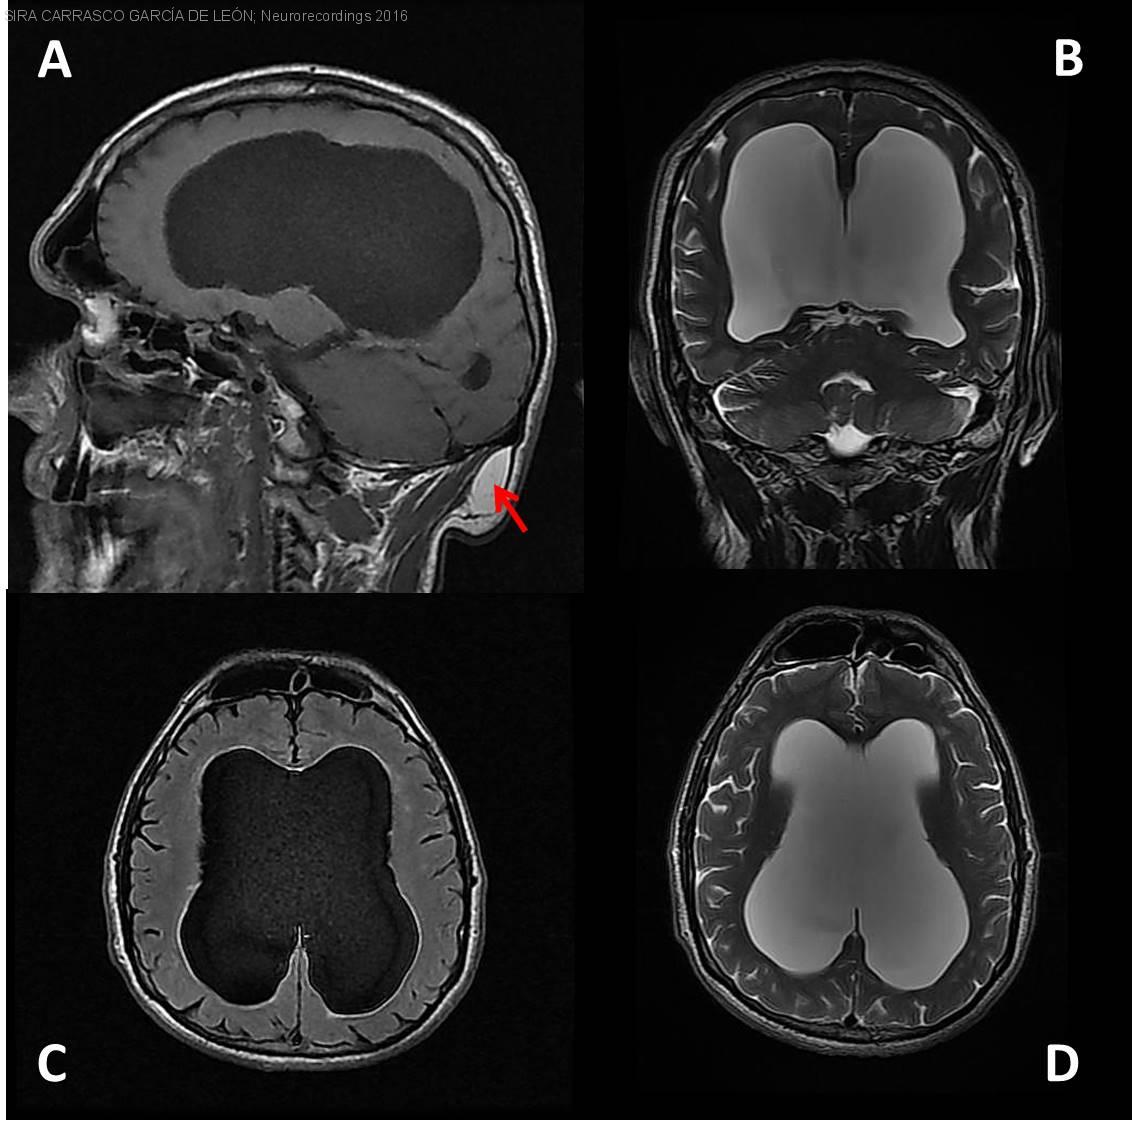

Diagnóstico final: Hidrocefalia triventricular crónica adquirida. Lipoma Subgaleal occipital

Varón de 48 años con antecedente de meningitis en la infancia. Remitido desde Atención Primaria para valoración de temblor en las manos desde hacía años.

En la exploración destacaba: papiledema crónico en el examen del fondo...